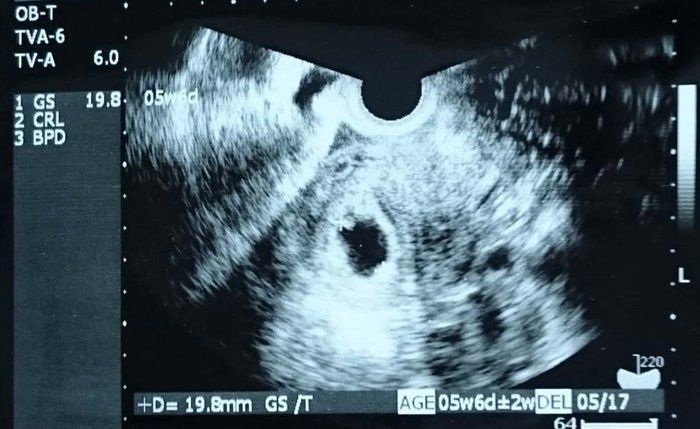

Tomomiさんの妊娠6週目のエコー写真 心拍確認できました

「ちゃんと大きくなっているかな?胎嚢の中に赤ちゃんは見えるかな?」不安な気持ちで内診台へ上がり、思わず手を組んで祈ってしまいました。先生のとっても嬉しそうな「おー、いたいた」という声にほっと胸を撫で下ろし、ピコピコ動くベビちゃん(胎児ネーム)の心拍を見ながら、「現実なのかな?」と信じられない気持ちでいっぱいでした。

私にとって4度目の妊娠陽性反応、そして初めての心拍確認!1つの大きな壁を乗り越えたと同時に、妊娠が継続するのかと、不安な気持ちと闘う日々も続くのでした…。

Tomomiさんの妊娠6週目のエコー写真 4日で3.9mmも成長!!

心拍確認から数日後、腰痛と少量の出血が起こり、急遽クリニックへ。「お願い…なんとかしがみついていてね…」と、祈る気持ちで診察を受けましたが、ベビちゃんは無事でした。たった数日での急成長に不安も吹き飛びました。

赤ちゃんがママから栄養をもらう“ホワイトリング”も見え、まさに天使のようでした(笑)。